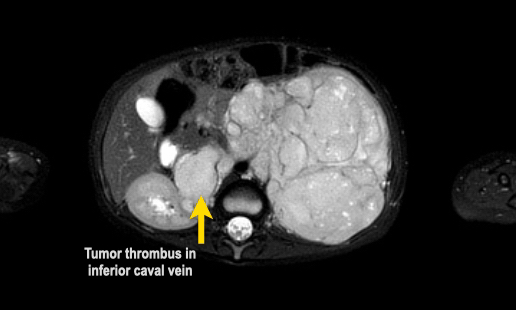

MRI có thể hiển thị rõ ràng huyết khối u trong tĩnh mạch thận và tĩnh mạch chủ dưới, cũng như tình trạng hạch bạch huyết to. Phương pháp này cho phép đo lường khối u một cách chính xác và có thể lặp lại trong các lần khám ban đầu và theo dõi.

Example 2

Video về một bé gái ba tuổi có khối u lớn ở hông phải.

Same patient.

A tumor thrombus is present in the inferior caval vein.

Chuỗi ảnh MRI axial trọng số T2 cho thấy huyết khối u lan rộng đến mức tĩnh mạch gan. Lưu ý phần còn lại giãn rộng của hệ thống thu thập nước tiểu